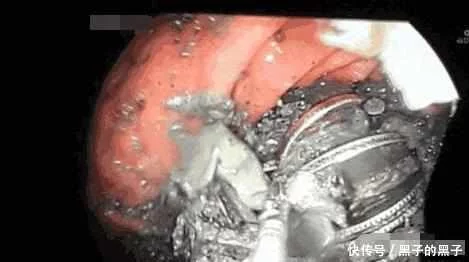

来到医院之后,医生先给她照了一个胃镜,看看女子到底是怎么回事,结果不看不知道,女子的胃里居然有奇怪的东西,夹在了胃里面,导致了女子的胃收缩的时候回非常的清楚。但是当医院仔细看清楚之后,发现了女子胃里的东西居然是铁块,医生看清之后马上吓到腿软了。叫女子离开这家医院,他们不敢做这个手速。